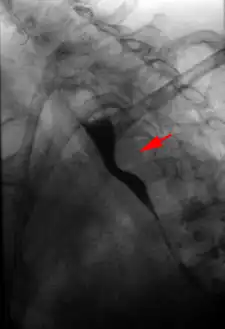

The evaluation of an aberrant subclavian artery can be done via CT angiography[7], which is a combo of CT scan with an injection of dye to produce images of blood vessels and/or tissues [8]

Surgery is occasionally used to treat the condition.[9]